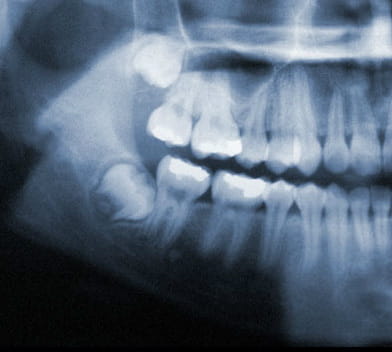

Wisdom Tooth Positions

Wisdom teeth under ideal circumstances should grow in straight like any other tooth. However, it is common for wisdom teeth to become impacted inside the jaw or just under the gums. If this occurs, your wisdom teeth should be removed.

Common Impactions:

- Horizontal Impaction

- Angular Impaction

- Vertical Impaction

- Soft Tissue Impaction